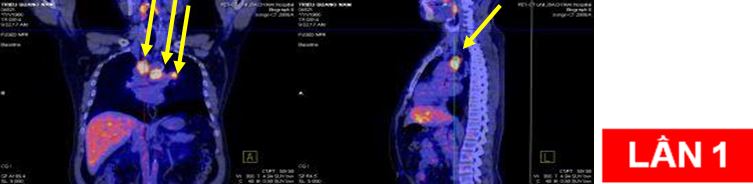

CHỤP PET/CT TOÀN THÂN

Hình ảnh khối u rốn u rốn phổi trái KT 4x4,5cm tăng hấp thu FDG mạnh, SUV=12,3.

Di căn hạch trung thất và hạch rốn phổi hai bên kích thước lớn nhất 2,5x3,6cm, SUV=6,8.

Di căn hạch trung thất tăng hấp thu FDG, nốt mờ thùy trên phổi trái tăng hấp thu FDG

Bệnh nhân:chụp PET/CT lần 2 đánh giá sau 6 chu kỳ hóa chất (có đối chiếu với lần chụp trước khi điều trị).

Trước và sau điều trị hóa chất 6 chu kỳ